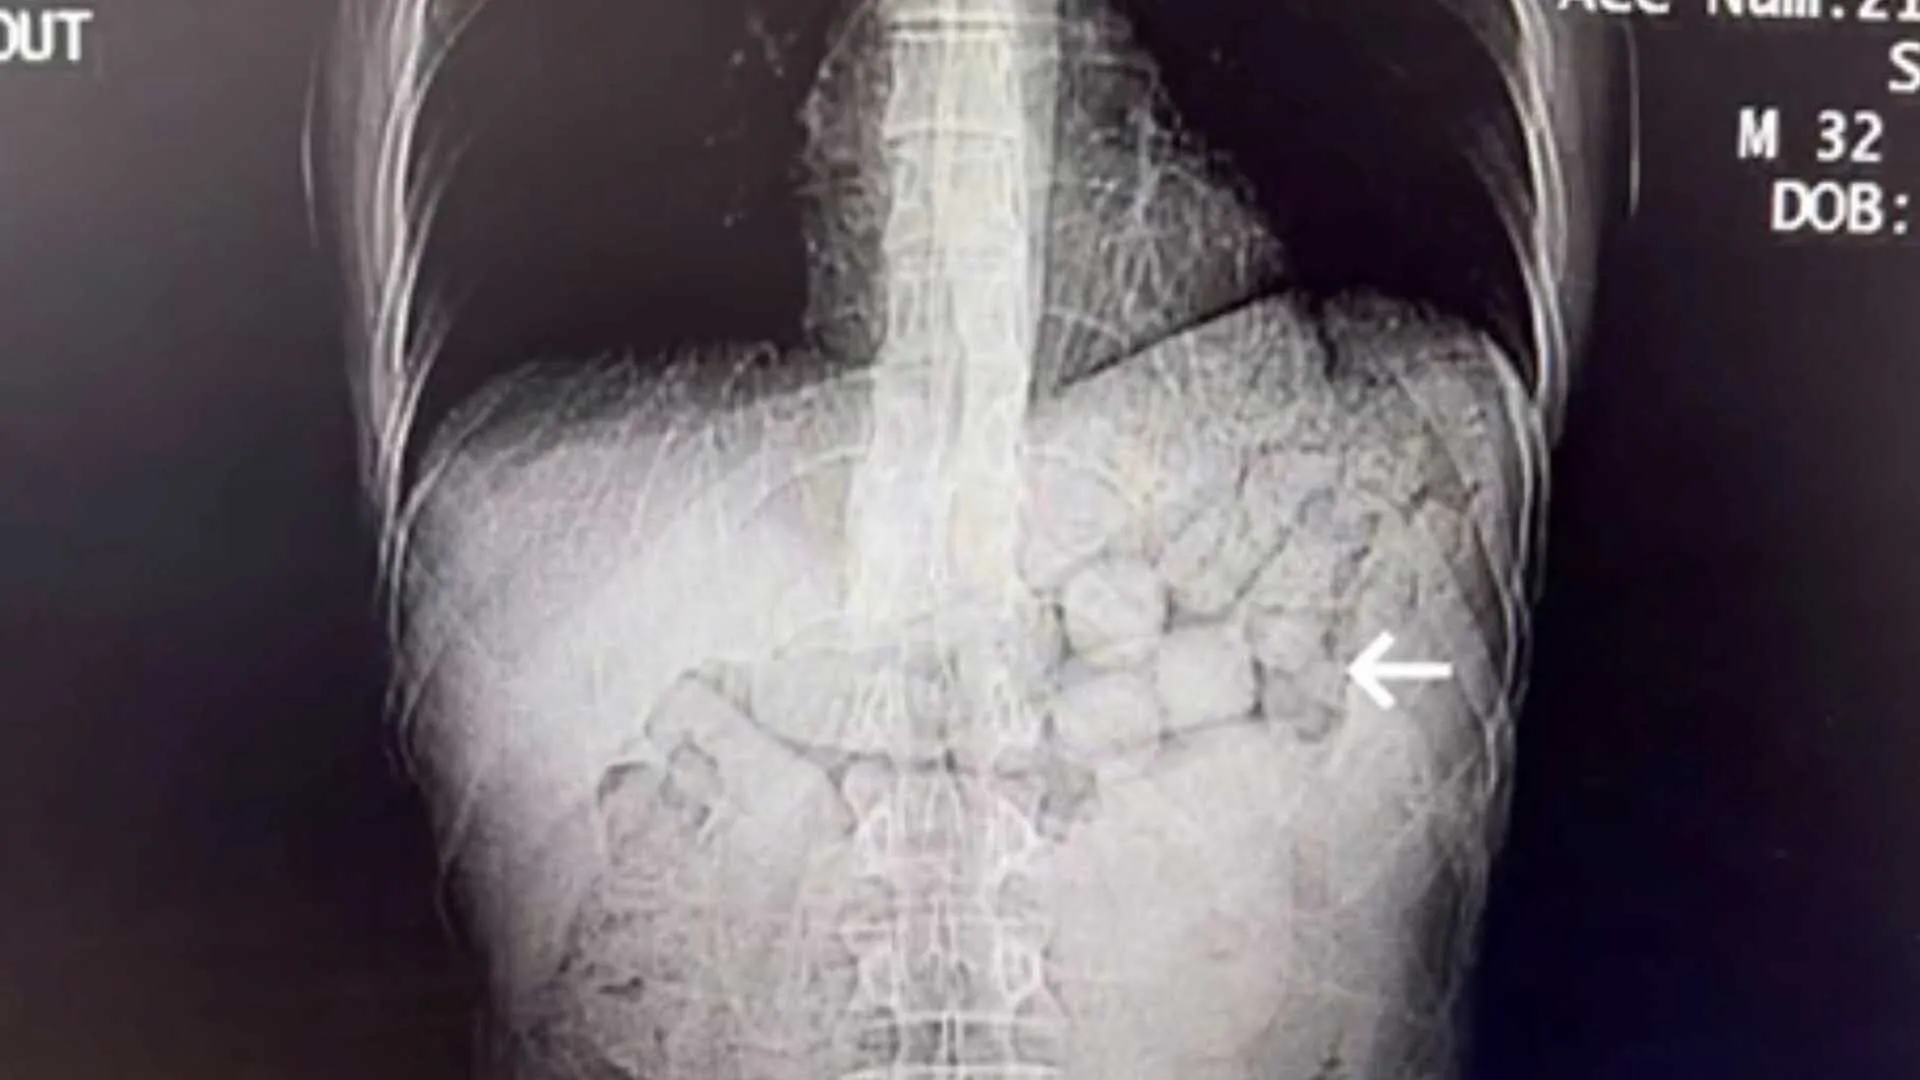

Hastanede çekilen tomografi görüntülerinde, şahısların mide ve bağırsak bölgelerinde yabancı cisimlere rastlandı. Yaklaşık 3 gün süren kontroller sonucunda, şüphelilerin vücutlarından 91 kapsül halinde toplam 807,15 gram metamfetamin maddesi çıkarıldı.